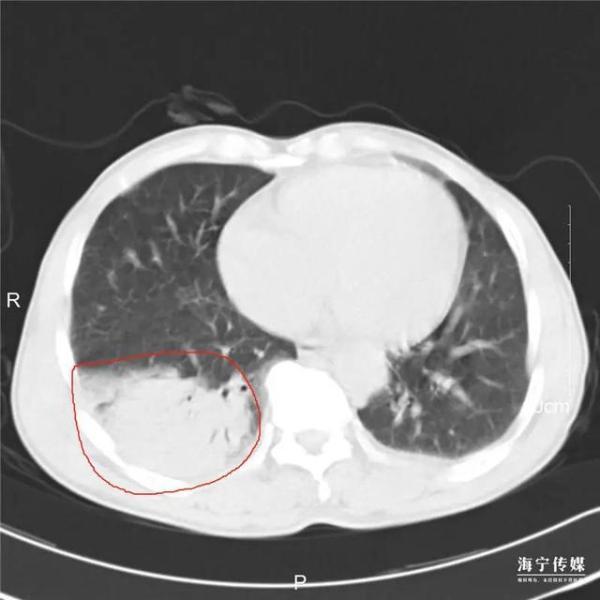

根据CT和血常规结果 , 海宁市人民医院呼吸内科主任孙亚红判断 , 老刘患上了肺炎 , 同时有特殊病原菌感染的可能 。 医生对他做了抗感染治疗 , 但治疗持续72小时 , 老刘的症状仍然在加重 , 肺部病灶也有进展 。

本文图片

△红圈圈出位置为病灶